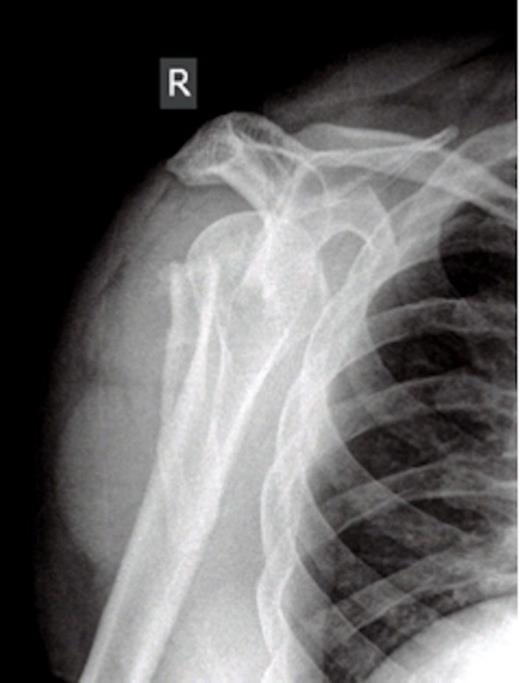

On examination there was restriction of the range of movement of the right shoulder with tenderness and swelling over the scapular. The skin was intact. There was no neurovascular deficit and the patient was otherwise physically well. X-rays revealed a fracture of the body of the scapula with posterior displacement of the inferior fragment. The shoulder joint was not dislocated and there were no associated fractures of the proximal humerus. The patient was admitted for analgesia and computed tomography was performed to assess the fracture. The scan showed involvement of the glenoid, with the fracture extending through the posterior lip. This was deemed inappropriate for surgical fixation. The patient was managed in a broad arm sling and discharged with simple range of movement exercises.